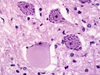

What is a gemistocyte?

***KNOW THIS***

Swollen astrocytes- cytoplasm contains pink “glassy” material